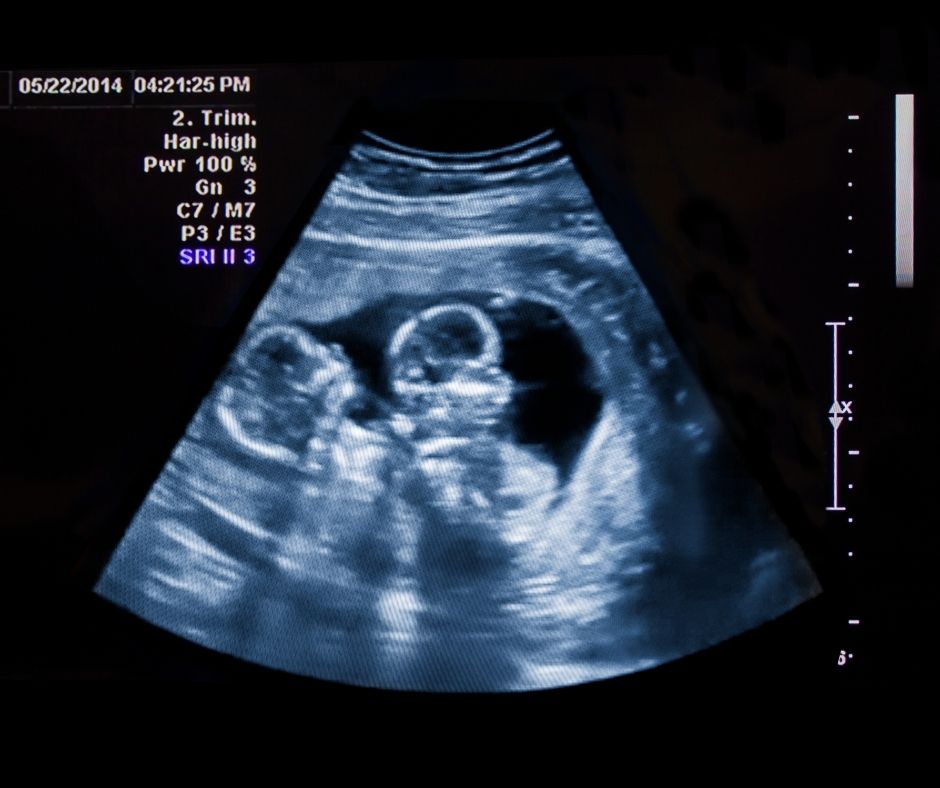

Ciąża wielopłodowa obraz USG - blog helloskarbie.pl

Ciąża bliźniacza w pierwszych trzech tygodniach może powodować mdłości i wymioty z uwagi na wyższy poziom beta-hcg. Po ukończeniu dwunastego tygodnia ciąży przyszła mama może potwierdzić swoje przypuszczenia o ciąży bliźniaczej na rutynowych badaniach USG. USG przy bliźniakach rozpoznaje nie tylko ilość pęcherzyków płodowych, ale i przybliżony wiek płodów, a także ewentualne wady wrodzone.